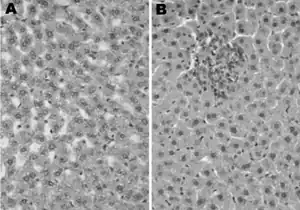

| TEM micrograph of Orthohepevirus A virions | |

The viral particles are 27 to 34 nanometers in diameter and are not enveloped.[2][4]